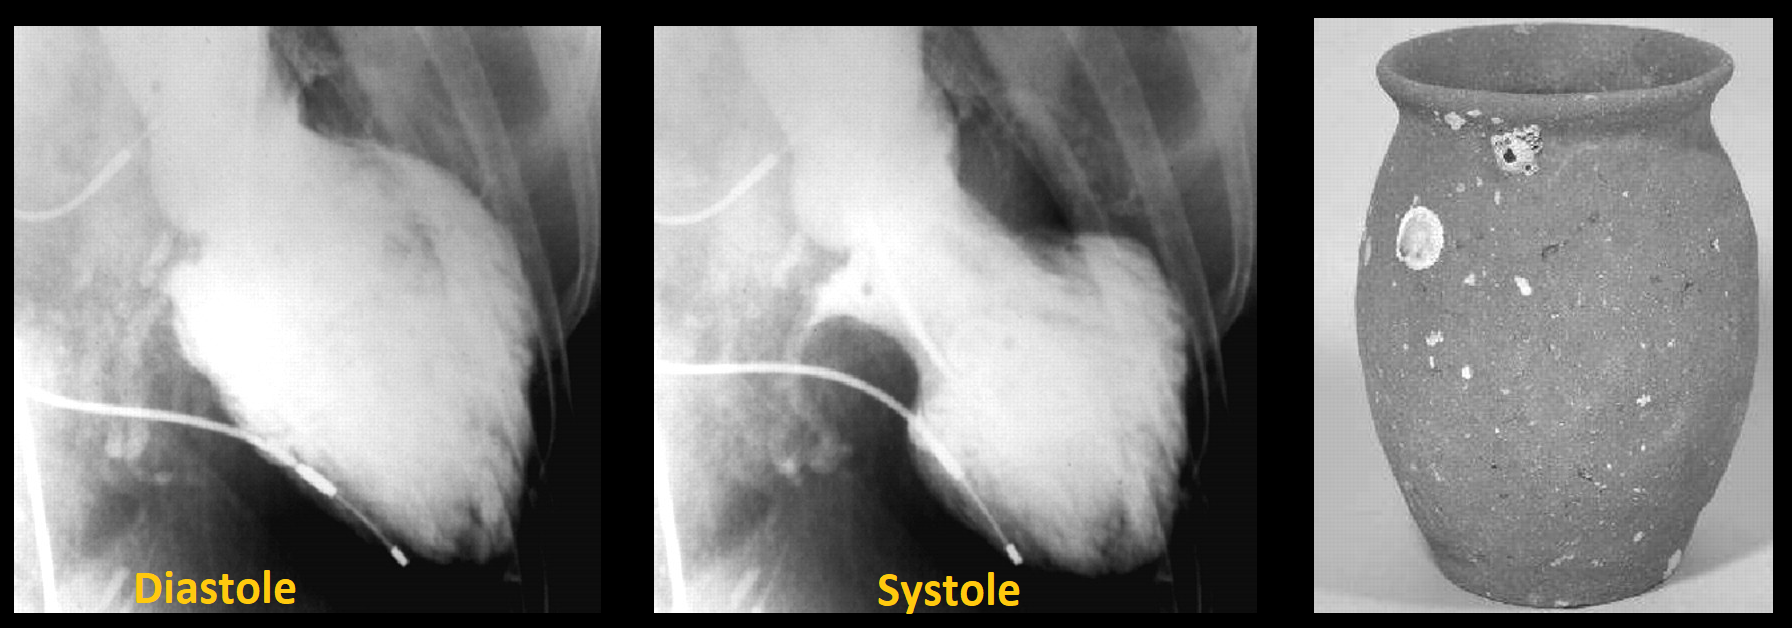

Syndrome du coeur brisé

- Femme post-ménopause (90%) suite à une forte émotion ++

- Akinésie / Hypokinésie de l’apex

- Aspect du coeur en piège à octopus en systole